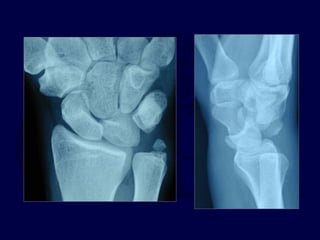

Imaging

โ€ข Note lack of โ€œcolinearityโ€

among the radius, lunate,

and capitate on the lateral

x-ray.

โ€ข Note loss of normal carpal

โ€œarcsโ€ and abnormal

widening of the scapholunate

interval.

โ€ข Look for associated fractures

โ€œtrans-scaphoidโ€ injuries

X-ray usually

Obvious

X-ray may be subtle